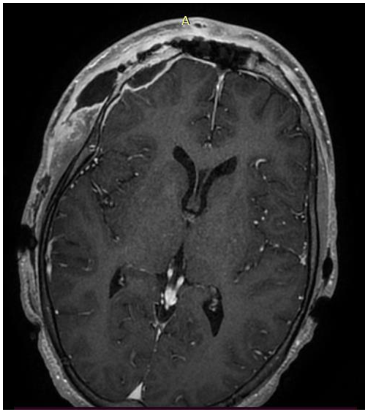

Imaging of Bilateral Thalamic Infarcts (Percheron Territory) and Differential Diagnosis (About Six Cases)

Asmae Rais, Fatima Saddouki, Nizar El Bouardi, Amal Akammar, Meriem Haloua, Badreddine Alami, Aouatef El Midaoui, Siham Bouchal, Mohammed Faouzi Belahsen, Meryem Boubbou, Mustapha Maaroufi and Moulay Youssef Alaoui Lamrani. 16(8): 01-13.